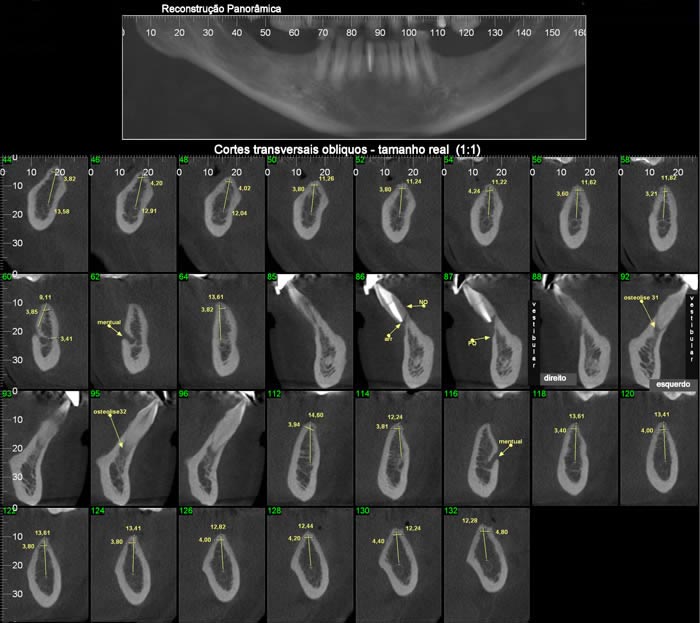

Nos softwares há ferramentas que permitem a reconstrução e a obtenção de novos cortes que mostram imagens de uso pontual na odontologia como os cortes transversais e longitudinais.

Os cortes transversais são cortes perpendiculares ao arco da maxila e mandíbula.

Na reconstrução panorâmica aparece uma régua no limite inferior que serve de localização para os cortes transversais.

Os cortes longitudinais são cortes no sentido vestíbulo lingual ou palatino, perpendiculares a uma reta traçada sobre o dente ou a área em questão.